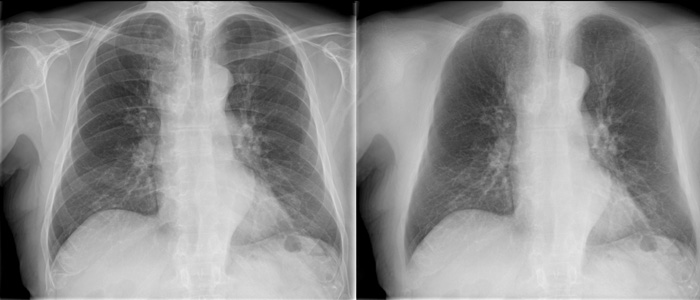

Grid-less imaging

SkyFlow Plus

A grid-less workflow with SkyFlow Plus.

SkyFlow Plus

A grid-less workflow with SkyFlow Plus.